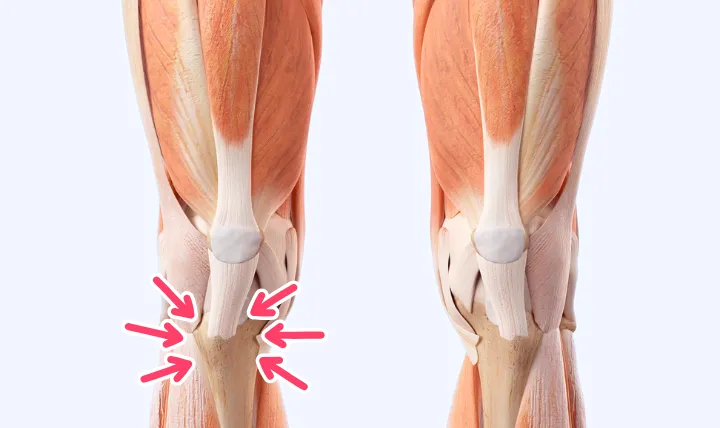

ジャンプやダッシュ、ボールを蹴る動作などで太ももの前の筋肉(大腿四頭筋)が繰り返し強く収縮すると、膝のお皿の下にある骨の付着部が引っ張られます。

成長期のお子さんはこの部分の骨がまだ柔らかい軟骨であるため、過度な負担がかかることで炎症が起き、痛みや腫れを引き起こすのです。

サイン②:膝下(すねの上)の骨がポコッと出っ張ってくる

炎症が続くと、常に引っ張られている膝下の骨の付着部が、徐々に隆起してきます。

痛くない方の脚と比べてみると、痛い方の膝下だけがポコッと出っ張っているのが分かるはずです。

この骨の隆起は、オスグッド病の最も

特徴的なサインの一つで、炎症が治まった後も、大人になっても残ることがあります。